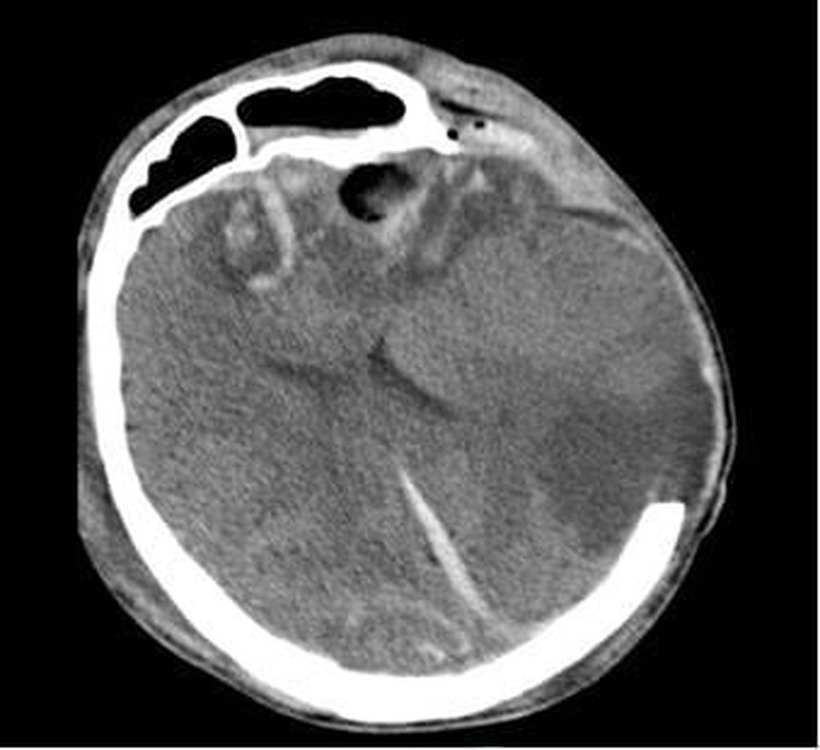

Phim CT não người bệnh G.A. ngày 06/01/2026 cho thấy dập não xuất huyết nhiều nơi, phù não lan tòa dù đã được mở sọ giải ép tối đa. Ảnh: Bệnh viện Nhân dân 115.

Người con trai, G.A. (28 tuổi), nhập viện trong tình trạng hôn mê sâu, phải thở máy. Kết quả chụp CT scan sọ não cho thấy dập não xuất huyết rải rác và phù não lan tỏa, đặt anh vào nguy cơ tử vong cao. Anh G.A. đã được điều trị tích cực tại Đơn vị Hồi sức Ngoại khoa, khoa Gây mê Hồi sức.